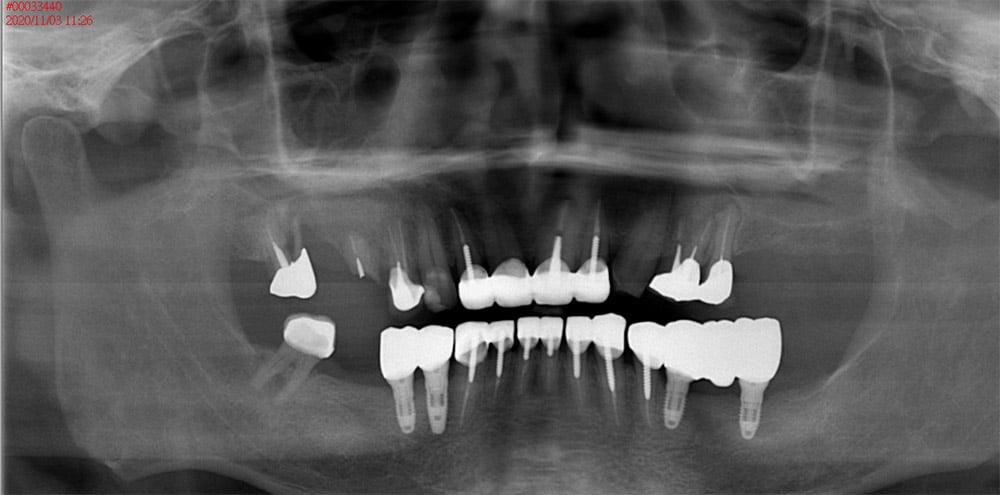

全口重建